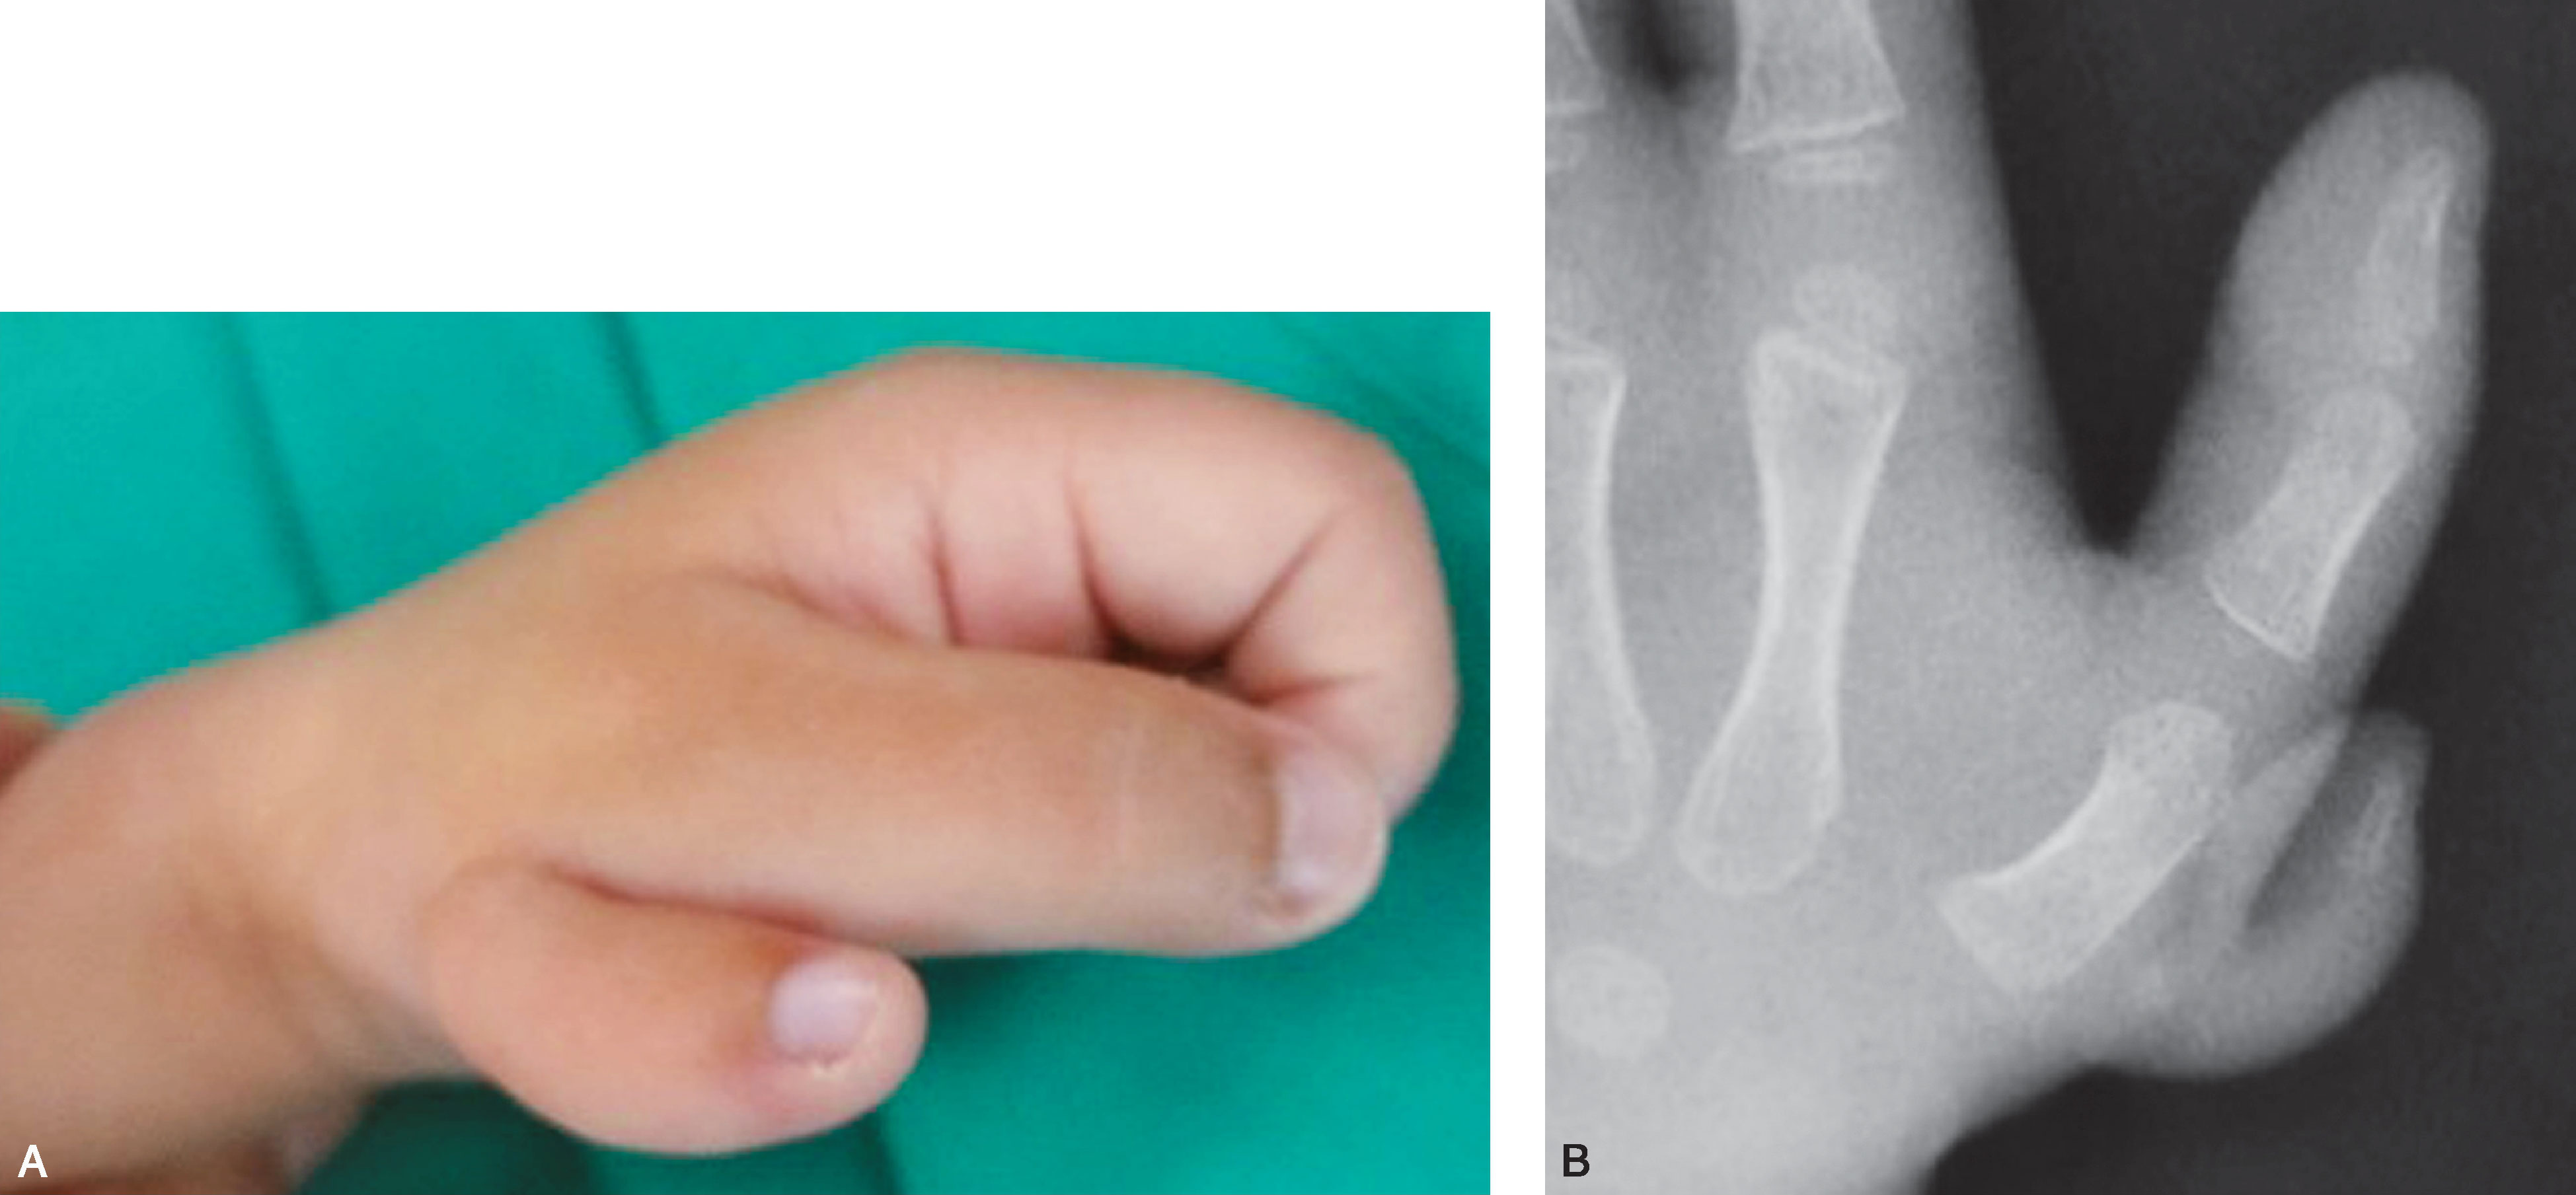

1.Ⅰ型 末节指骨未完全分裂,近节指骨正常或不正常,共用一个骨骺,并与近节指骨远端形成关节(图2-1-1~图2-1-4)。

图2-1-1 Ⅰ型病例1

A.主拇指与次拇指外形差异较大,各自有独立的指甲,远节尺偏(左侧);B.X 线片显示,虽然指骨远端分开,但基底共用一个骨骺,重建时需手术切除部分桡侧骨骺板,远节指骨尺偏需行近节指骨远端桡侧闭合楔形截骨,以纠正远节手指的尺偏畸形